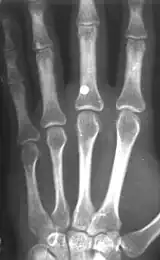

A BB with a velocity of only 45 m/s (150 ft/s) has skin-piercing capability, and a velocity reaching 60 m/s (200 ft/s) can fracture bone.[7] This is potentially lethal, and this potential increases with velocity, but also rapidly decreases with distance. The effective penetrating range of a BB gun with a muzzle velocity of 120 to 180 m/s (390 to 590 ft/s) is approximately 18 m (60 ft). A person wearing jeans at this distance would not sustain serious injury. However, even at this distance a BB still might penetrate bare skin, and even if not, could leave a severe and painful bruise. The maximum range of a BB gun in the 120 to 180 m/s (390 to 590 ft/s) range is 100–200 metres approximately,[8] provided the muzzle is elevated to the optimum angle.